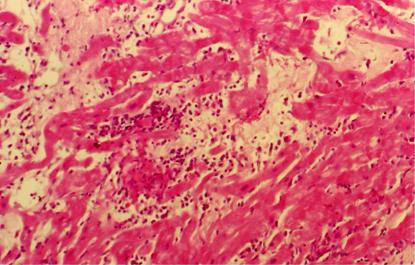

La diagnosi di rigetto miocardico viene effettuata mediante le biopsie endomiocardiche, che vengono effettuate periodicamente nel follow up e che permettono di stabilire il grado di rigetto presente ed il protocollo farmacologico da instaurare.

RIGETTO GRADO III A